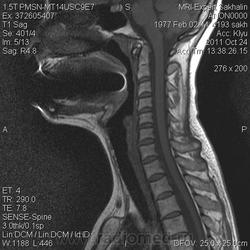

1. Субархноидальная киста

2. Лизированная субдуральная гематома.

3. Менее вероятнее эпиема (но это только при условии соотвествующей клиники...)

Такая огромная гематома на 2 отдела?

Думаю все же №1... № 2 - это запасной вариант. Послушаем, что скажет общественность

Мультилокулярная экстрадуральная менингеальная киста